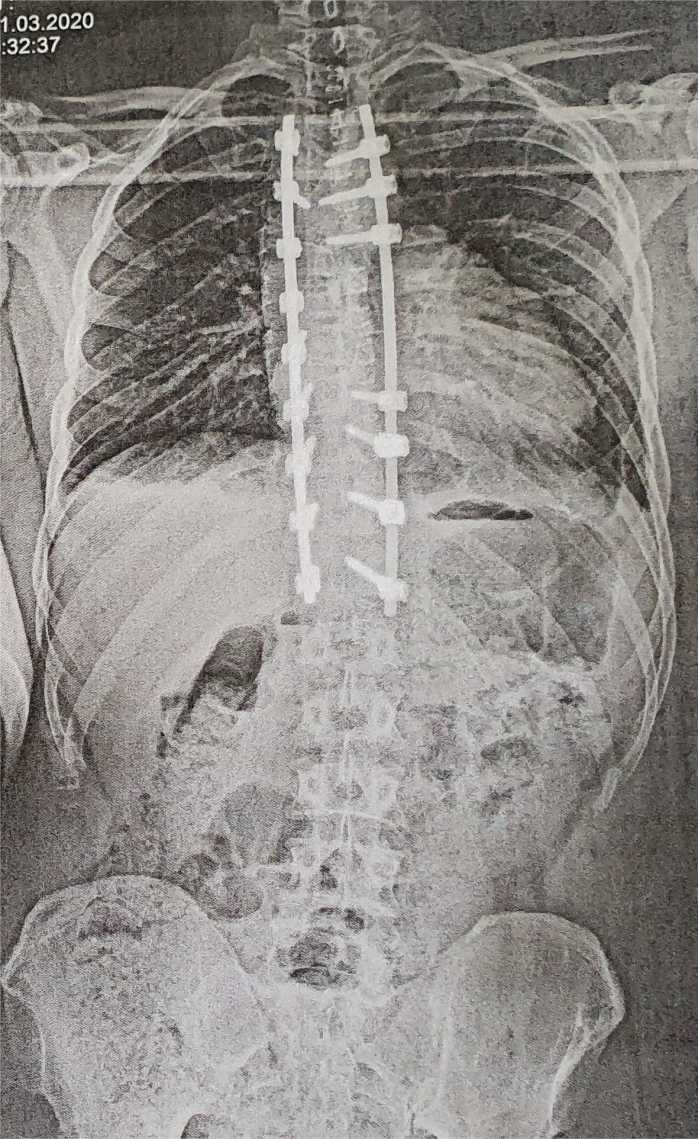

Die OP fand Anfang März statt. Es wurde von Th4 bis Th12 versteift und auf 7° und 9° korrigiert. Die Rotationskomponente konnte ebenfalls sehr gut korrigiert werden, sodass ich zum ersten Mal in meinem Leben ein halbwegs symmetrisches Skelett habe. Ferner wurde sehr sorgsam auf mein sagittales Profil geachtet, wodurch ich von einem Fast-Flachrücken nun auf einen Kyphosewinkel von 25° komme.